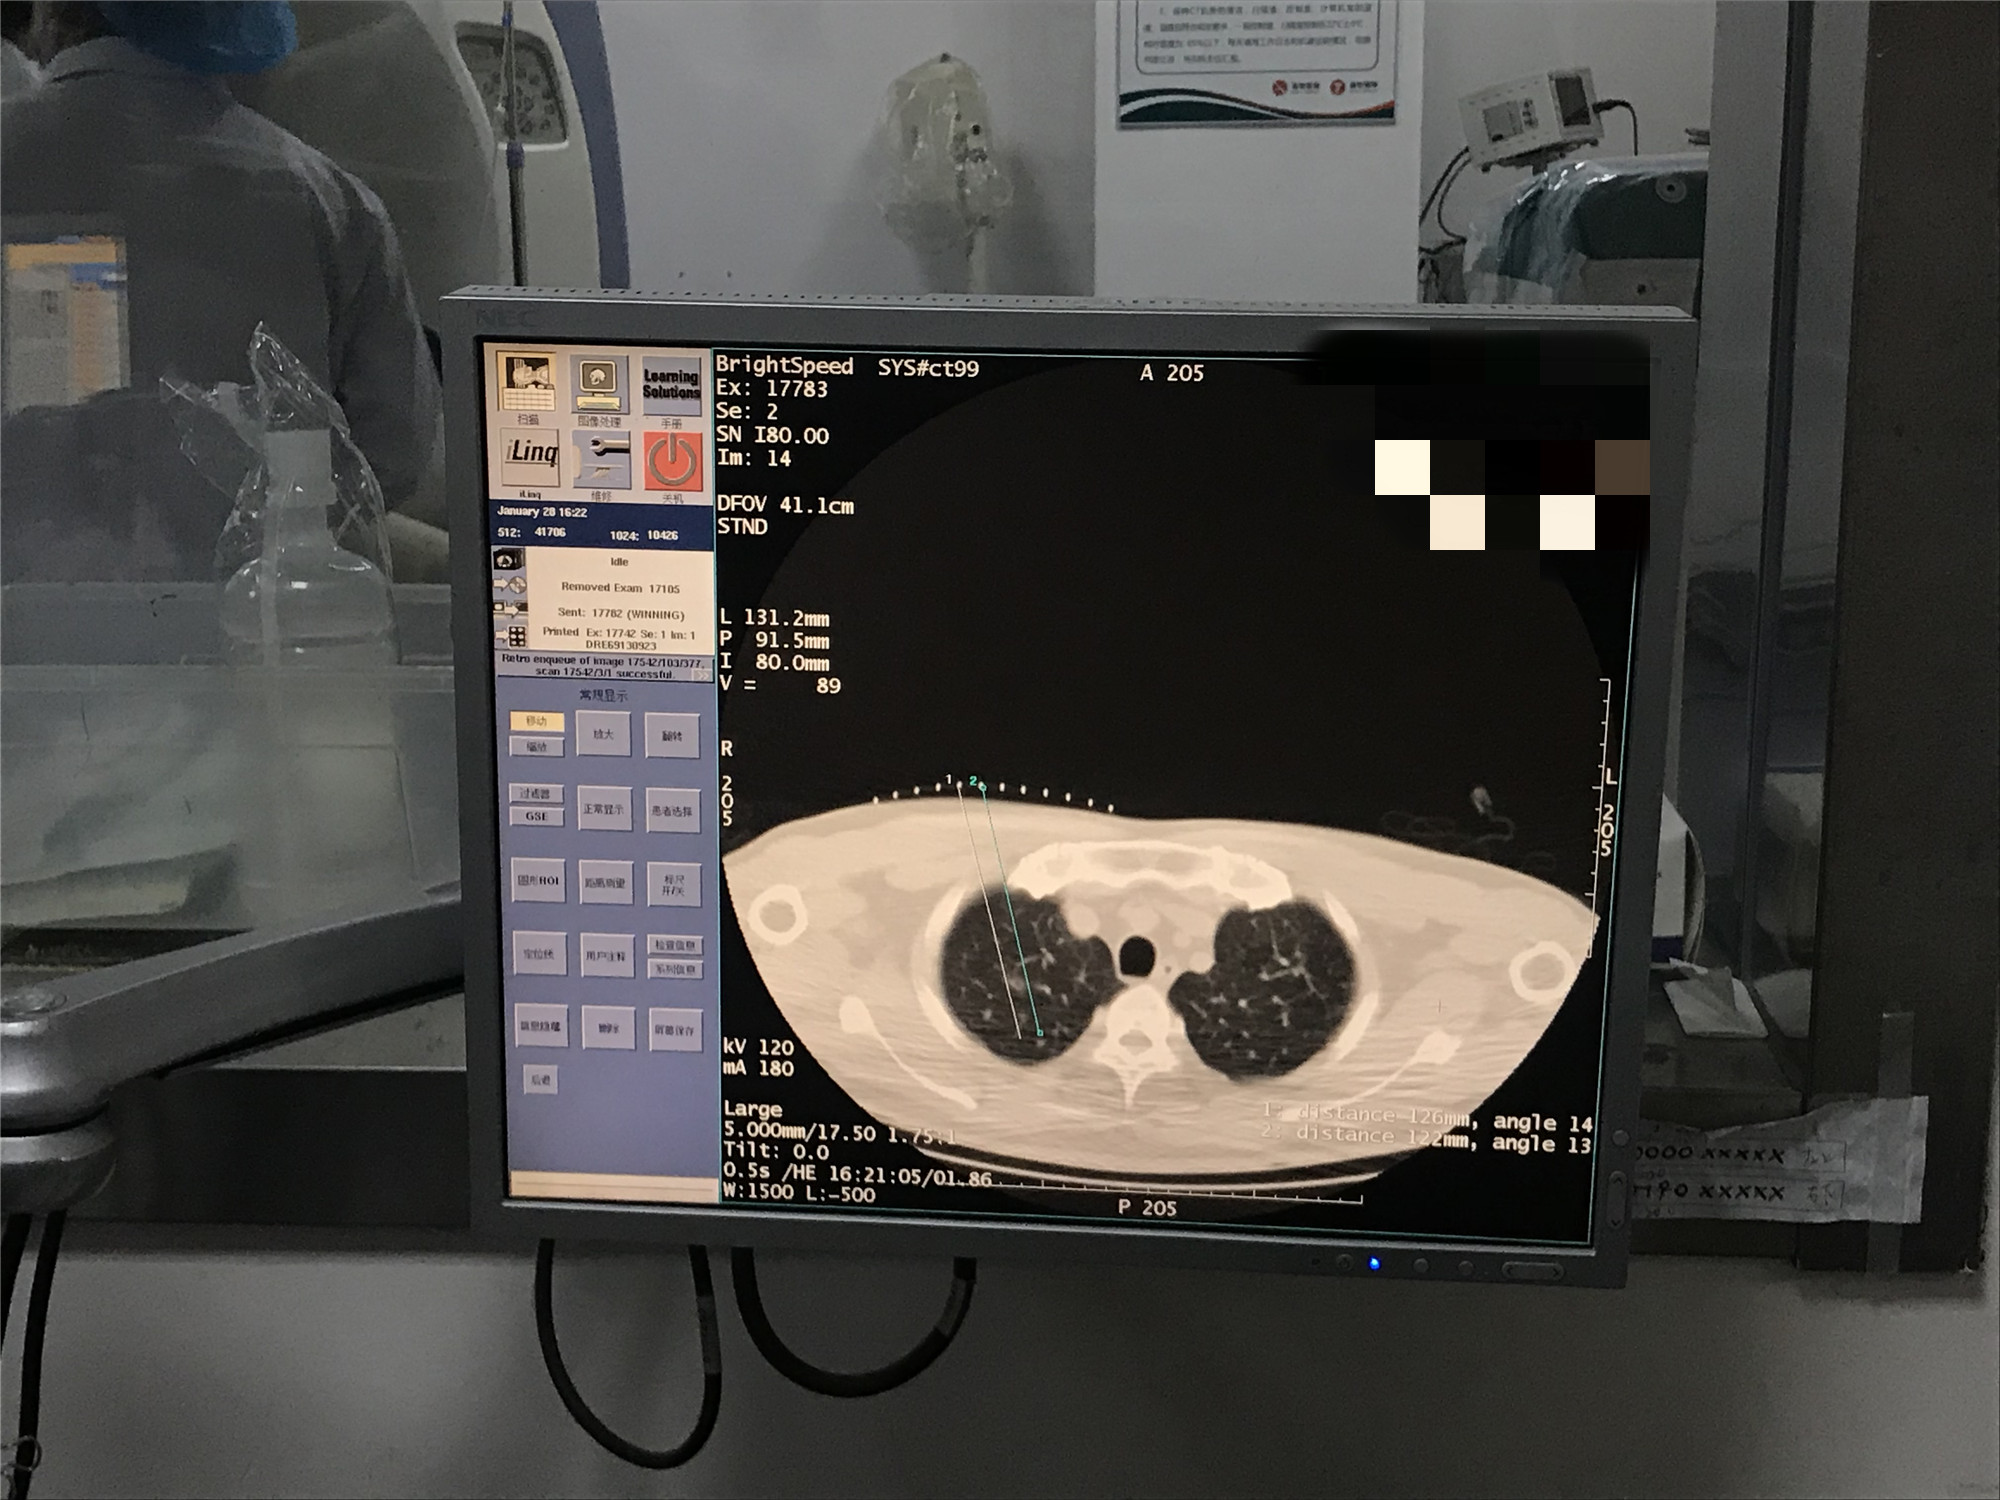

2021年1月份肺部氩氦刀手术